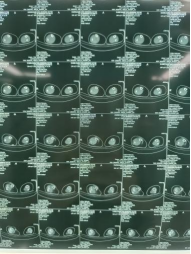

患者男性,54歲,外傷致右側(cè)脛腓骨開放性骨折8小時,局部可見右側(cè)脛骨骨折近端露出,小腿部肌肉部分損傷外露,皮膚損傷,脛神經(jīng)損傷。CT顯示右側(cè)脛腓骨遠端粉碎骨折,累及關(guān)節(jié)面,骨折斷端分離移位,成角移位。